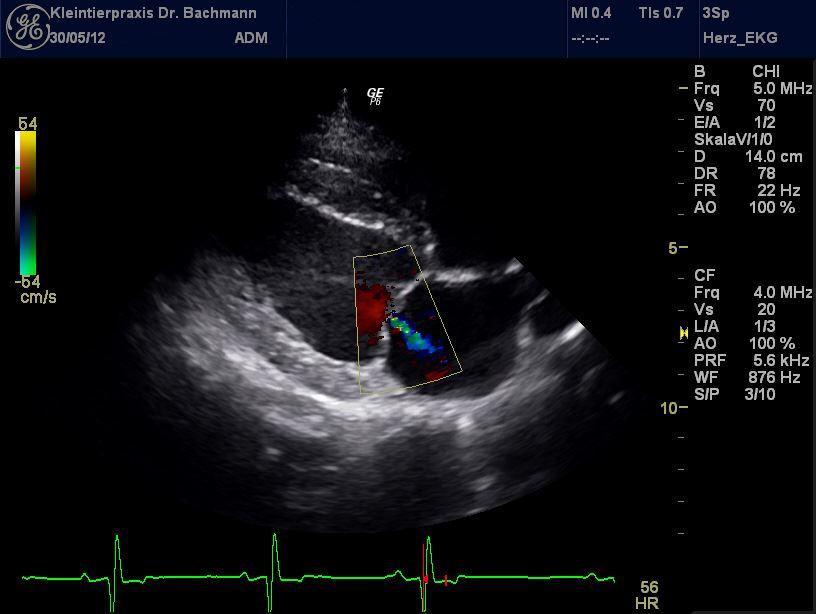

Kardiologische Erkrankungen betreffen Tiere aller Altersstufen. Neben angeborenen Defekten, sind verschiedene Rassen genetisch für unterschiedliche Erkrankungen am Herzen prädisponiert (z.B. der Dobermann für DCM, Cavalier King Charles-Spaniel für Klappendefekte oder die Maine Coon Katze für HCM) und alle Tiere können im Alter von unterschiedlichen Herzerkrankungen betroffen sein. Die Untersuchung mittels Herzultraschall (Echokardiographie) ist die einzige diagnostische Möglichkeit, diese Erkrankungen exakt darzustellen, den Zustand des Herzens zu beurteilen und eine adäquate Therapie einzuleiten. Ergänzend zur immer an erster Stelle stehenden Auskultation (Abhören des Herzens), kommen die Röntgenuntersuchung, die Blutdruckmessung und die Bestimmung spezifischer Herzparameter im Blut zum Einsatz.